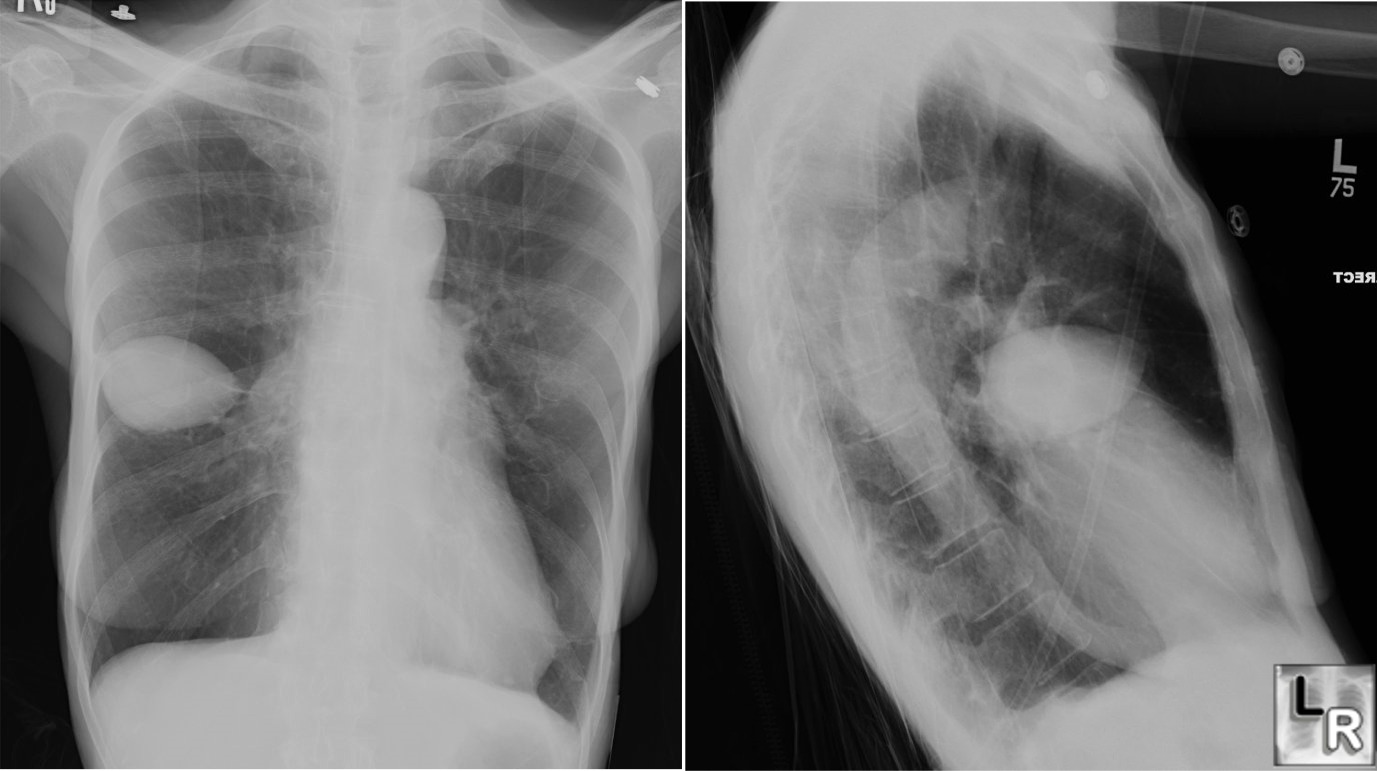

Pseudotumor, Vanishing Tumor, Effusion, Minor Loculated Effusion Chest X Ray Most frequently it is caused by a loculated pleural effusion (pleural pseudotumor) trapped in the pleural fissures. On the image, loculated pleural effusion may. Detection of pleural effusion(s) and the creation of an initial differential diagnosis are highly dependent upon imaging of the pleural. Out of concern for malignancy, exploration of the. Obliteration of left costophrenic angle with a wide. Loculated Effusion Chest X Ray.

(A) Xray chest, posteroanterior view, with fissural effusion, and (B Loculated Effusion Chest X Ray Detection of pleural effusion(s) and the creation of an initial differential diagnosis are highly dependent upon imaging of the pleural. Most frequently it is caused by a loculated pleural effusion (pleural pseudotumor) trapped in the pleural fissures. Obliteration of left costophrenic angle with a wide pleural based dome shaped opacity projecting into the lung noted tracking along the. On the. Loculated Effusion Chest X Ray.